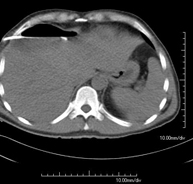

- Tórax- TC Tórax Prueba diagnóstica que consiste en obtener imágenes del tórax de alta definición anatómica (pulmones, corazón, mediastino, grandes vasos, caja torácica, etc.) mediante el empleo de un equipo de TC (Tomografía Computarizada). Dichas imágenes se estudian posteriormente en una estación de trabajo que permite reconstrucciones bidimendionales en diferentes planos del espacio y también reconstrucciones 3D (volumétricas). Algunos estudios requieren el empleo de contraste yodado para mejorar la definición de las imágenes. Prueba diagnóstica que consiste en obtener imágenes del tórax de alta definición anatómica (pulmones, corazón, mediastino, grandes vasos, caja torácica, etc.) mediante el empleo de un equipo de TC (Tomografía Computarizada). Dichas imágenes se estudian posteriormente en una estación de trabajo que permite reconstrucciones bidimendionales en diferentes planos del espacio y también reconstrucciones 3D (volumétricas). Algunos estudios requieren el empleo de contraste yodado para mejorar la definición de las imágenes.

- TC Tórax alta resolución Prueba diagnóstica que consiste en el estudio del pulmón mediante el empleo de un equipo de TC (Tomografía Computarizada) obteniendo imágenes bi y tridimensionales que permiten un estudio anatómico altamente específico del pulmón, pudiendo valorar estructuras anatómicas de tamaño muy pequeño. Es una técnica muy importante en el estudio de los pacientes con sospecha de enfermedad pulmonar. Prueba diagnóstica que consiste en el estudio del pulmón mediante el empleo de un equipo de TC (Tomografía Computarizada) obteniendo imágenes bi y tridimensionales que permiten un estudio anatómico altamente específico del pulmón, pudiendo valorar estructuras anatómicas de tamaño muy pequeño. Es una técnica muy importante en el estudio de los pacientes con sospecha de enfermedad pulmonar.